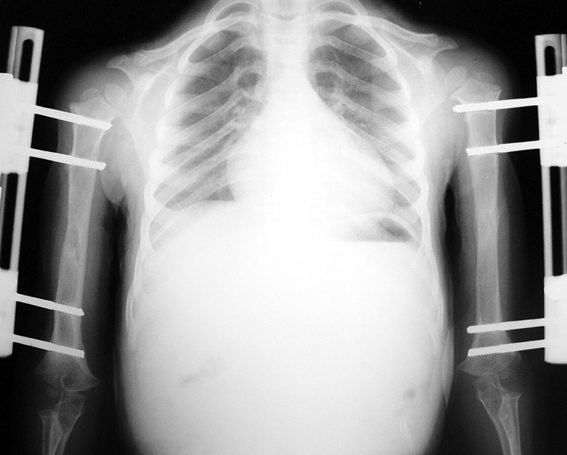

13-15 yaşlar arasında Her iki humerusu (kol) 8-12 cm boy uzatma Dirseklerin fleksiyon deformitesini düzeltme Ortalama eksternal fiksasyon tedavi süresi = 6-8 ay Alt uzuvların iki uzatması arasında üst uzuvlar uzatılarak alt uzuvların dinlenmesi sağlanmış olur. Cihaz çıkartıldıktan sonra en erken ikinci uzatmaya başlama süresi 6 aydır. Bilateral femoral uzatmalarda uzatma fazı sırasında hastanın yürümesi mümkün değildir. Ayakta durmaya sadece hasta transferi sırasında izin verilir. Uzatma fazında ambulasyona sadece tekerlekli sandalye ile izin verilir. Konsolidasyon fazında ise tedrici olarak daha fazla yük verilmesine ve cihazın çıkmasına yakın serbest yürümeye izin verilir. Bilateral tibial uzatmalarda ilk günden itibaren yürüteç veya koltuk değneği ile hastanın yük vermesine izin verilir. Uzun gezintiler tekerlekli sandalye ile yapılmalıdır. Bilateral humeral uzatmalarda hemen hemen hiçbir aktivite kısıtlaması yoktur. Uzatma süresince her iki haftada bir yapılan takiplerde kantitatif duyusal sinir testleri doktor tarafından yapılmalıdır. Bu gelişmekte olan sinir sorunlarını klinik olarak ortaya çıkmadan yakalamaya izin verir. Femoral ve humeral uzatmalarda çok nadir görülmesine rağmen tedavi edilmedikleri durumda düşük ayağa (ayağı yukarı çeken kasları innerve eden sinirin felci) neden olabilirler. Eğer erken tespit edilir ve uzatmanın hızı azaltılırsa, sinir problemi genellikle kendiliğinden düzelir ve uzatmaya düşük hızda devam edilir. Uzatmada yavaşlamaya rağmen sinir problemi devam ederse sinirin cerrahi olarak gevşetilmesi gerekir. Bu işlem 1cm’ lik bir kesi ile yapılabilen ve hastanede bir gece kalmayı gerektiren küçük bir işlemdir. Bu ameliyat el bileğinde sinir sıkışması (karpal tünel sendromu) için yapılana benzerdir.